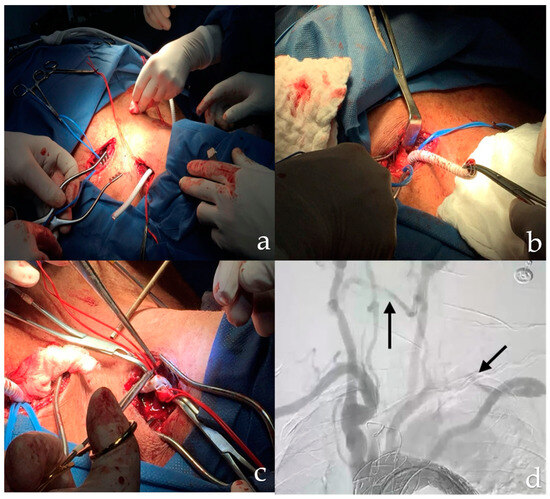

2. Detailed Case Description